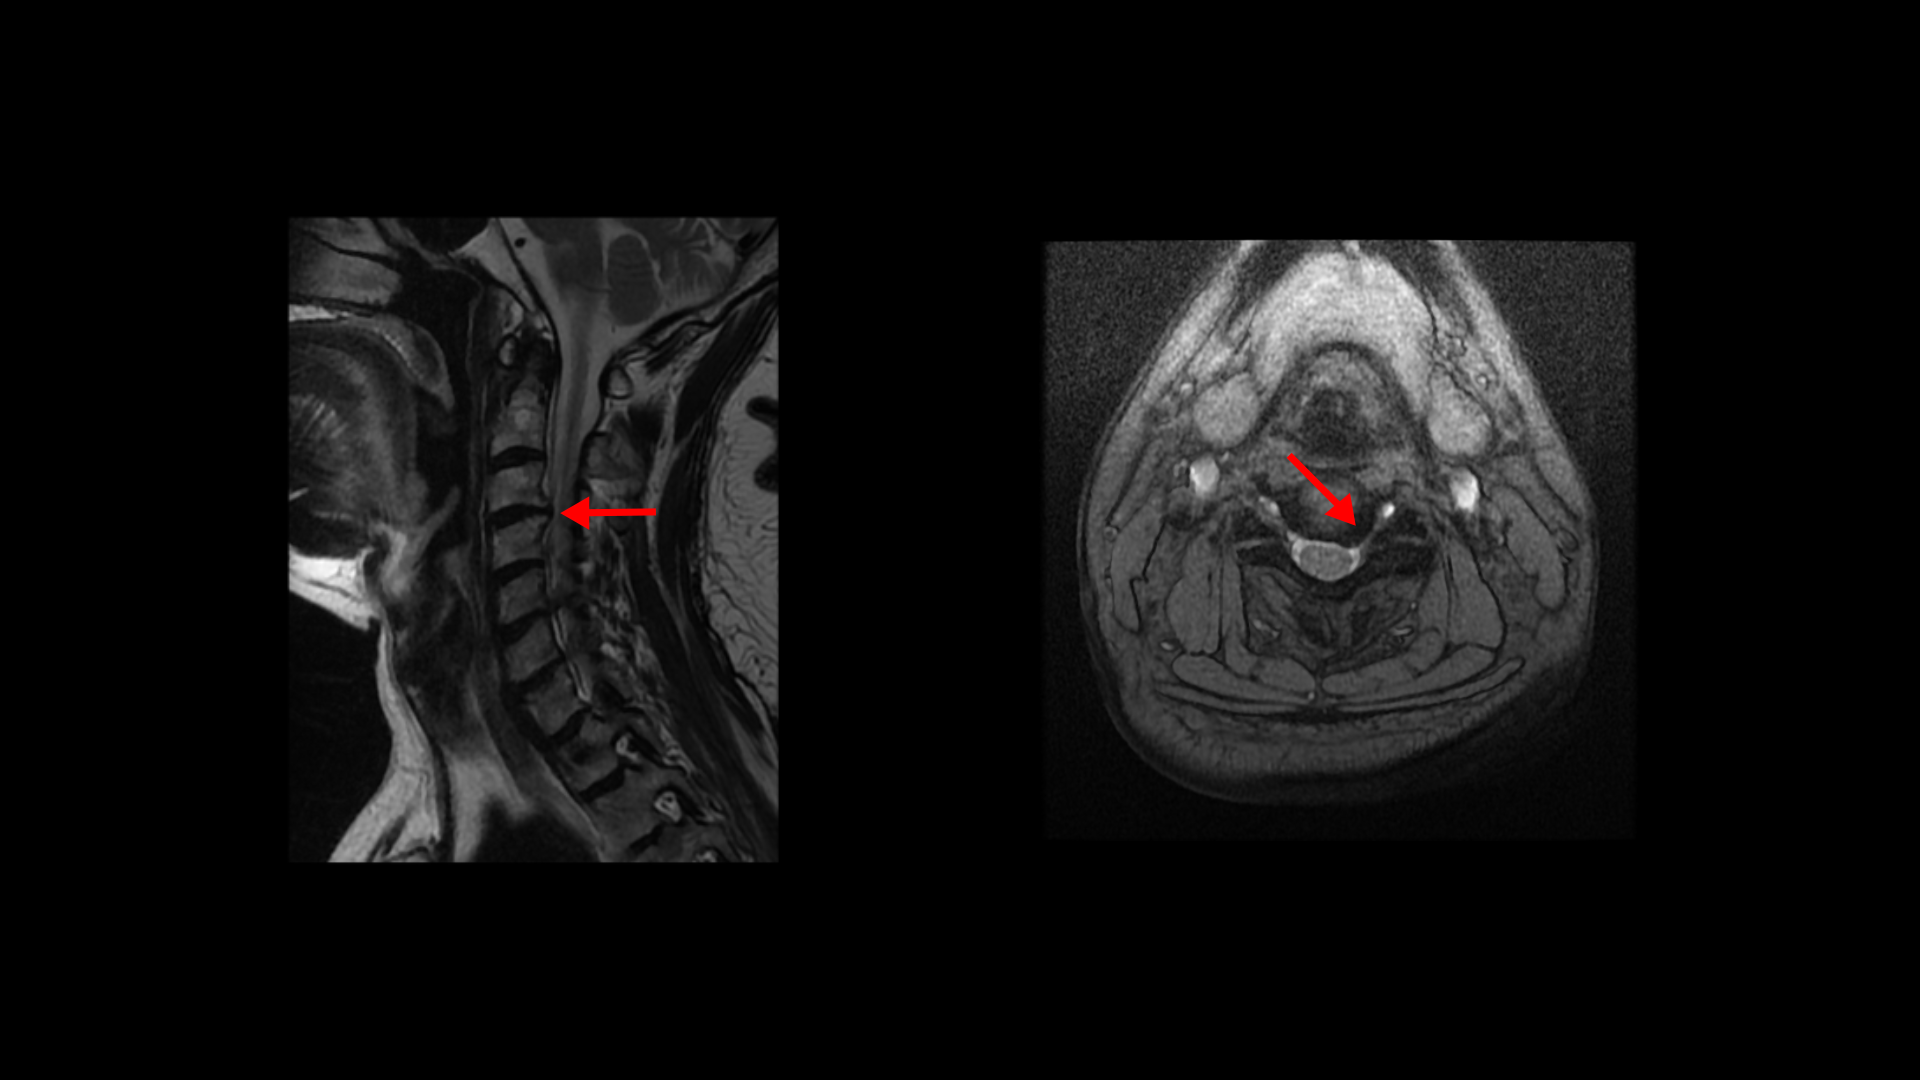

제가 먼저 이 환자분의 상태에 대해 설명드린 후 이분 말씀 더 들어보겠습니다. 이 환자분은 정말 오래된, 본인 표현으로는 30년된 심한 여러 마디의 목디스크와 또 허리에는 2마디의 퇴행성 디스크 및 추간공협착이 있습니다. 목디스크는 MRI로 보면 3번 4번 목디스크가 뼈가 심하게 자라면서 밀려나와있고 왼쪽으로 나가는 신경길을 막고 있습니다.

5번 6번 디스크도 왼쪽으로 심하게 밀려나와 있습니다. 이분 왼쪽 팔의 힘 빠짐 증상은 이것 때문인 것으로 보입니다.